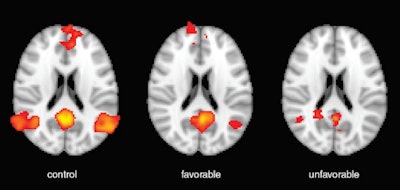

The fMRI scans focused on specific networks in the brain, including the default mode network, which is active when a person is not engaged in a specific task, and the salience network, which consists of a collection of brain regions that select which stimuli are deserving of one's attention.

Regarding connectivity between the brain networks, one key predictor of outcomes was the interaction between the default mode and salience networks. Normally, as the default mode network becomes more active, the salience network becomes less active and vice versa.

Patients with favorable outcomes had greater preservation of connectivity within the default mode network (p = 0.002) and higher levels of connectivity between the salience and default mode networks (p < 0.001) than patients with unfavorable outcomes.

"The distribution and magnitude of tissue signal change on FLAIR and on DWI were both directly linked to the probability of recovery," Stevens said. "However, the changes in network functional connectivity that we identified were stronger outcome predictors."